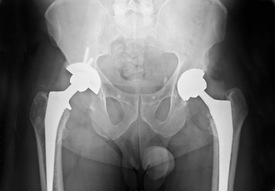

Hip replacement surgery is a fairly common procedure in the United States and quite a few makers of these devices have manufactured products that have held up for years without issue, however the Zimmer Durom Cup used in Hip replacement surgery has shown a very high rate of failure causing patients to require hip replacement revision surgeries along with possible pain and other side effects. These problems can be stressful and mentally traumatizing.